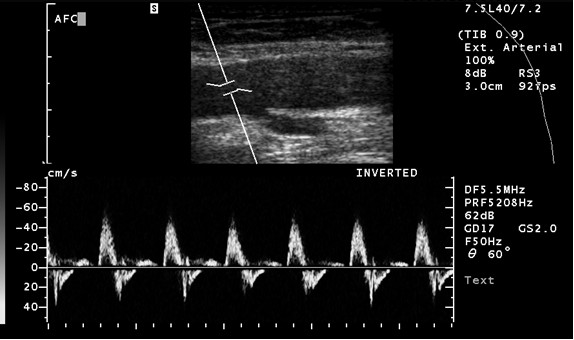

Pacjent zgłosił się po poradni naczyniowej z powodu okresowo występujących zawrotów głowy, występujących głównie podczas wysiłku. W badaniu przedmiotowym stwierdzono obecność cichego szmeru skurczowego w okolicy rękojeści mostka. Tętno na obydwóch kończynach górnych wyczuwalne. Próba Adsona ujemna. Wykonano badanie dupleksowe tt szyjnych i kręgowych. Podczas badania naczyń kręgowych po stronie lewej uzyskano przedstawiony poniżej obraz. Należy go zinterpretować jako: